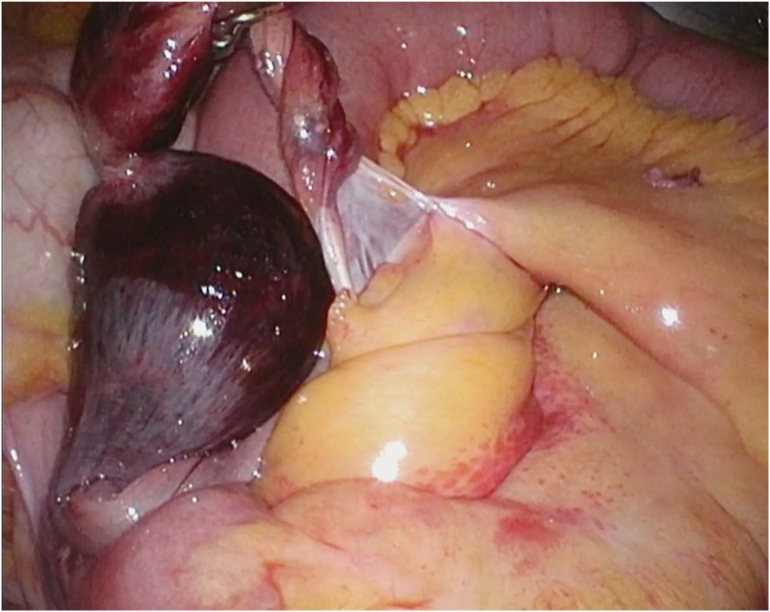

Surgical findings: The patient was operated on under general anesthesia in the supine position with both hands open. A 12-mm port was placed in the umbilicus, 5-mm ports were placed in the left lateral abdomen and mid-lower abdomen, and a 5-mm flexible speculum was inserted through the left lower abdominal port to observe the intra-abdominal cavity. Generally, the small intestine was markedly dilated throughout, and intraperitoneal observation suggested that the cause for this was a band-associated internal hernia of the small intestine. The band was continuous with Meckel's diverticulum at the mouth 60 cm from the end of the ileum and was necrotic due to torsion. The small intestine was released, the band was separated with an ultrasonic coagulation incision device, and the root of Meckel's diverticulum was resected with a 45-mm linear stapler. The operation was conducted laparoscopically and took 1 h 31 min for completion; a blood loss of 5 mL was noted (Fig. 2).

Fig. 2.

The Meckel's diverticulum appears tortuous and necrotic. A mesodiverticular band is noted.